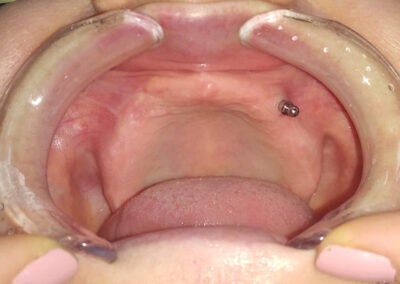

Proteze na implantima

Osim što predstavlja estetski problem, bezubost gornje vilice narušava normalnu funkciju celokupnog organizma, narušavajući zdravlje. Ukoliko nema adekvatne obrade hrane u usnoj duplji, ceo gastrointestinalni sistem je ugrožen. Kada nema zuba, visina zagrižaja se gubi, vilični zglobovi se opterećuju na pogrešan način, a lice dobija starački izgled.

Pacijentkinja se javila u našu ordinaciju da joj pomognemo. Kod nas je došla bez protetskog rada u gornjoj vilici.

Imala je problematičnu situaciju gde je teško uraditi protetski rad, čega je pacijentkinja i bila svesna jer je nekoliko puta do sada pokušavano, čak i uz pomoć implanata, ali bezuspešno.

Iskoristili smo stari implant i uradili novu protezu poštujući sve kliničke faze izrade proteze. Ova proteza pacijentkinji sada konačno služi u funkciji govora i žvakanja.